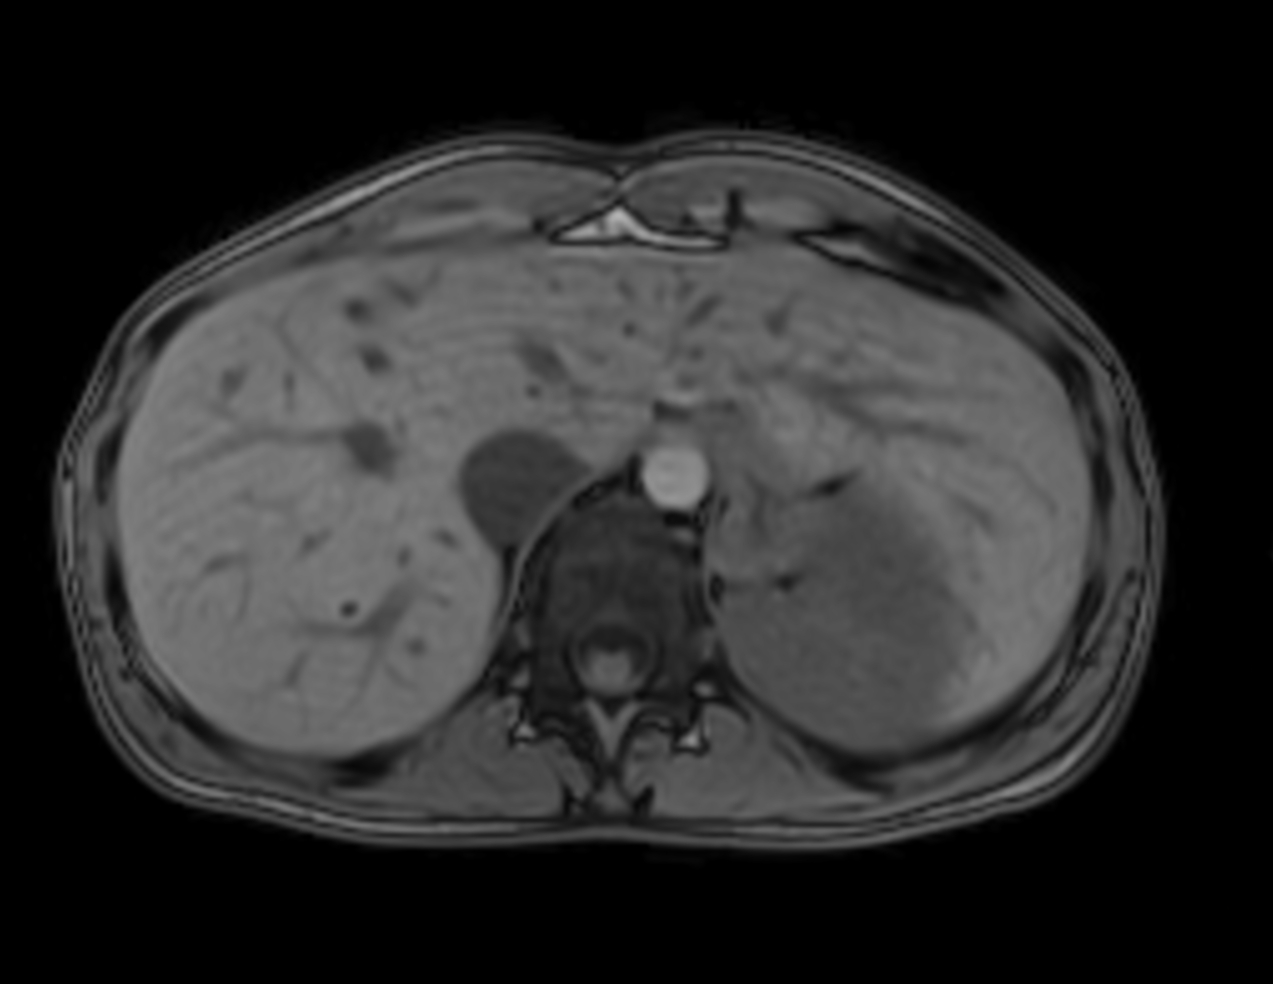

Axial mDIXON XD - T1w FFE (Water only)